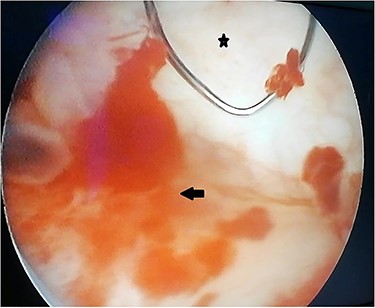

A 55-year-old, nonsmoking patient with no medical or surgical history who had a pulmonary adenocarcinoma diagnosed 1 month prior was referred to the urology department for macroscopic hematuria. Actually, the patient had initially presented with hemoptysis and a computed tomography (CT) scan revealed a right lower lobar pulmonary nodule, which biopsies concluded to a moderately differentiated adenocarcinoma. Interrogation revealed urinary frequency, urgency and several episodes of intermittent hematuria for 3 months. Physical examination showed a patient with an impaired general condition, without other abnormalities and a normal urine color. The urine dipstick revealed a hematuria at two crosses. The biological workup showed no abnormalities and the prostate specific antigen (PSA) level was at 2 ng/ml. The thoracic-abdominal-pelvic CT scan, performed for his lung cancer, showed, in addition to the lung mass of the right lower lobe with a right mediastinal adenopathy, a thickening of the bladder wall enhancing on the right lateral wall, an upper urinary tract free of any lesion and no distant metastases (Fig. 1). Cystoscopy under locoregional anesthesia was performed, showing a normal endoscopic appearance of the urethra and prostate gland, with inflammatory and bullous lesions on the bladder trigone and right lateral wall, which were biopsied using a resector (Fig. 2).

Peroperative appearance during cystoscopy before resection. Star: healthy bladder mucosa. Arrow: bullous inflammatory lesion that was resected.